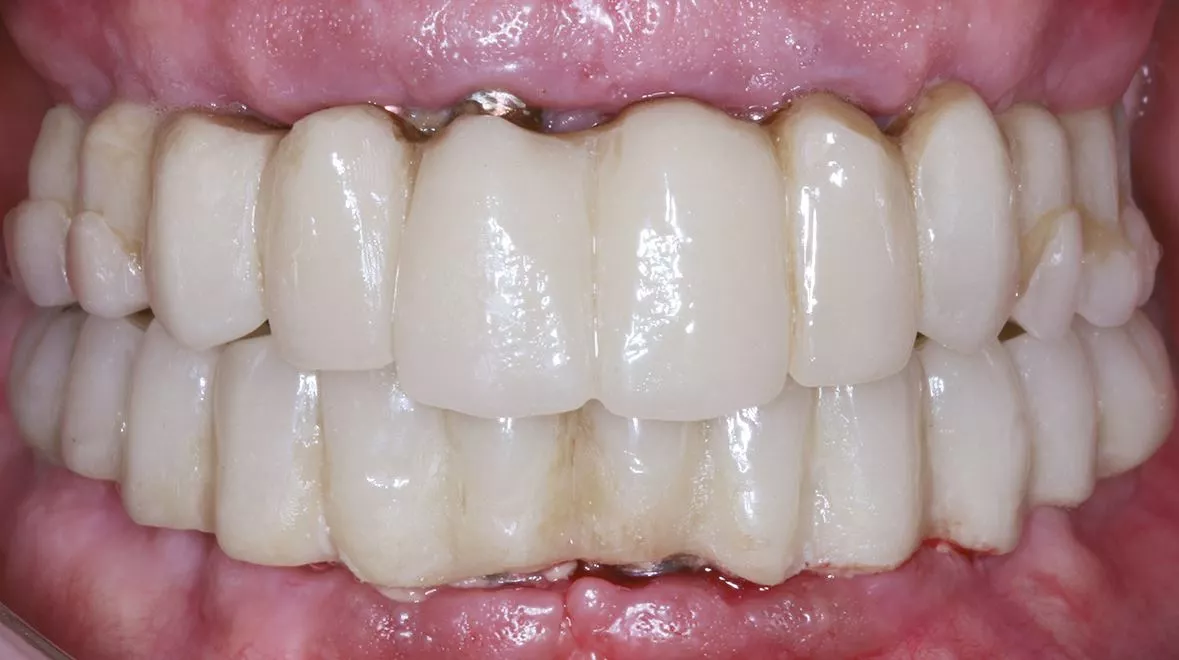

im Oberkiefer bei dünner Kortikalis oftmals durch ein festeres Einpressen positioniert werden. Im Unterkiefer wird über die Hülse für den Fixationspin in der Regel eine Vorbohrung notwendig. Nach der genauen Lagesicherung der Navigationsschablone kann dann die komplette Bohrerabfolge geführt bis zur Implantatinsertion angewendet werden. Im Anschluss werden die bei der Planung definierten geraden und angulierten Abutments eingesetzt und die Titanzylinder für das Einkleben des Provisoriums fixiert [1]. Nach dem Einkleben der Zylinder in das Provisorium muss diese nochmals ausgearbeitet werden und die Sofortversorgung ist abgeschlossen (Abb. 11-12).

In einem nächsten Schritt kann man dann eine geführte Einzelzahnsofortversorgung durchführen. Der gezeigte Fall stellt den Abschluss einer solchen Entwicklung dar. Die Plattform erleichtert dem Anwender auch komplexe Versorgungen mit vertretbarem Aufwand sicher und mit einem geringen Komplikationsrisiko zu erreichen (Abb. 13-14). Nach einer Einarbeitung mit dem digitalen Workflow, können dann wieder je nach Investitionsvolumen Arbeitsschritte in der eigenen Praxisstruktur etabliert werden, um den Leistungsumfang wieder stärker in der praxiseigenen Prozesskette einzubinden.